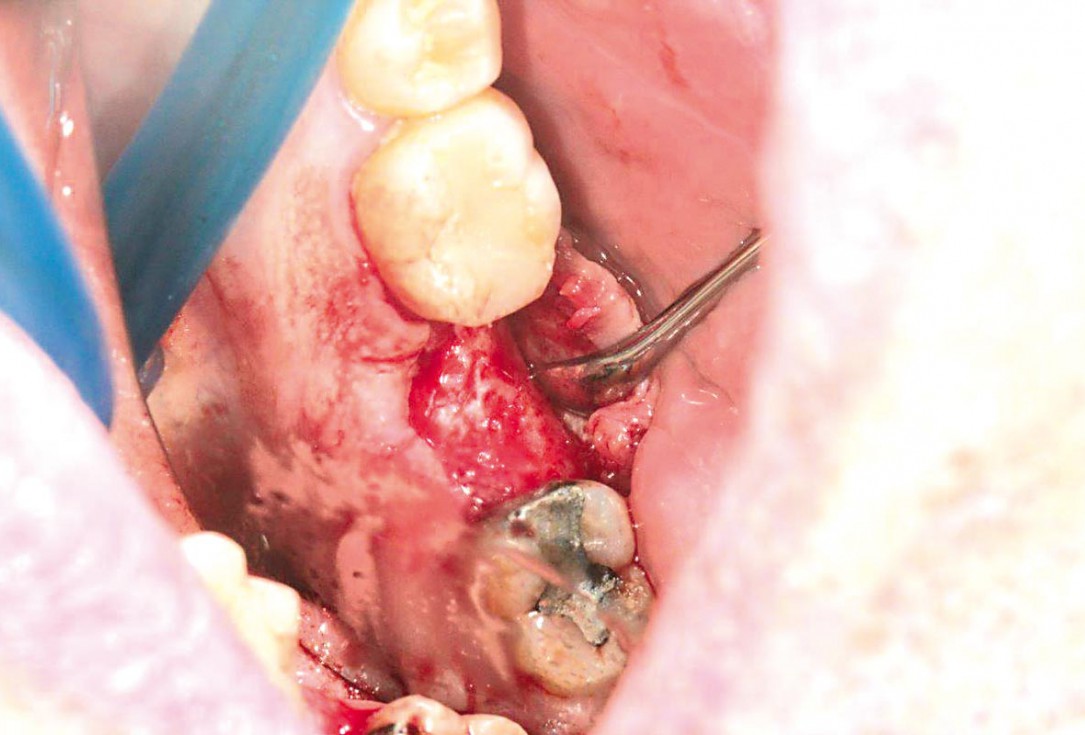

botiss cerabone® & collagen fleece for immediate implantation - Clinical case by Dr. D. Jelušić

Clinical situation before extraction and implantation